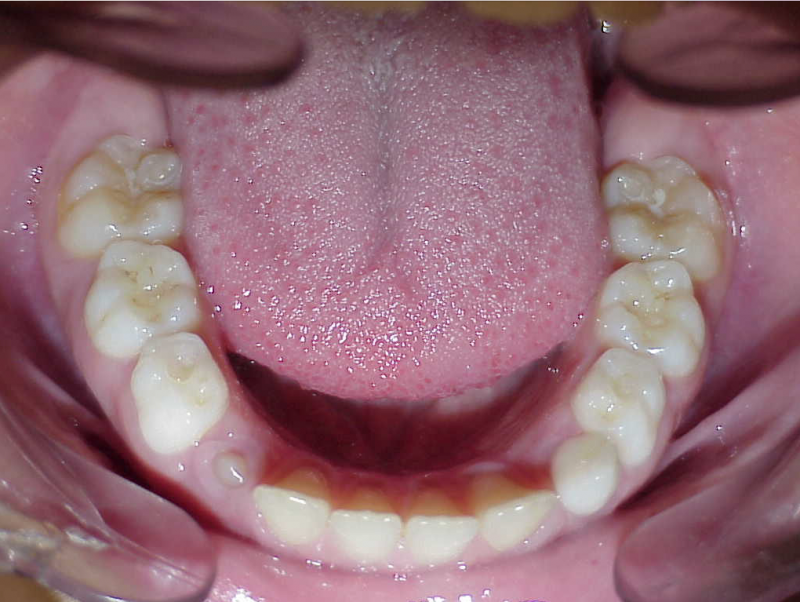

Behandeling Hajar

eindfoto

Beschrijving

Leeftijd bij aanvang: 9 jaar

1-6 maanden Bonded Hyrax in de bovenkaak, banden/slotjes in de onderkaak met Transforce

7-13 maanden: Twinblock

14-47 maanden: Volledig banden/slotjes in de boven-en onderkaak (omdat er hier blijvende kiezen ontbraken moesten er kiezen getrokken worden en de ontstane ruimtes gesloten, dit verklaart de langere behandeltijd)

Retentie fase: Wrap en C-CBar